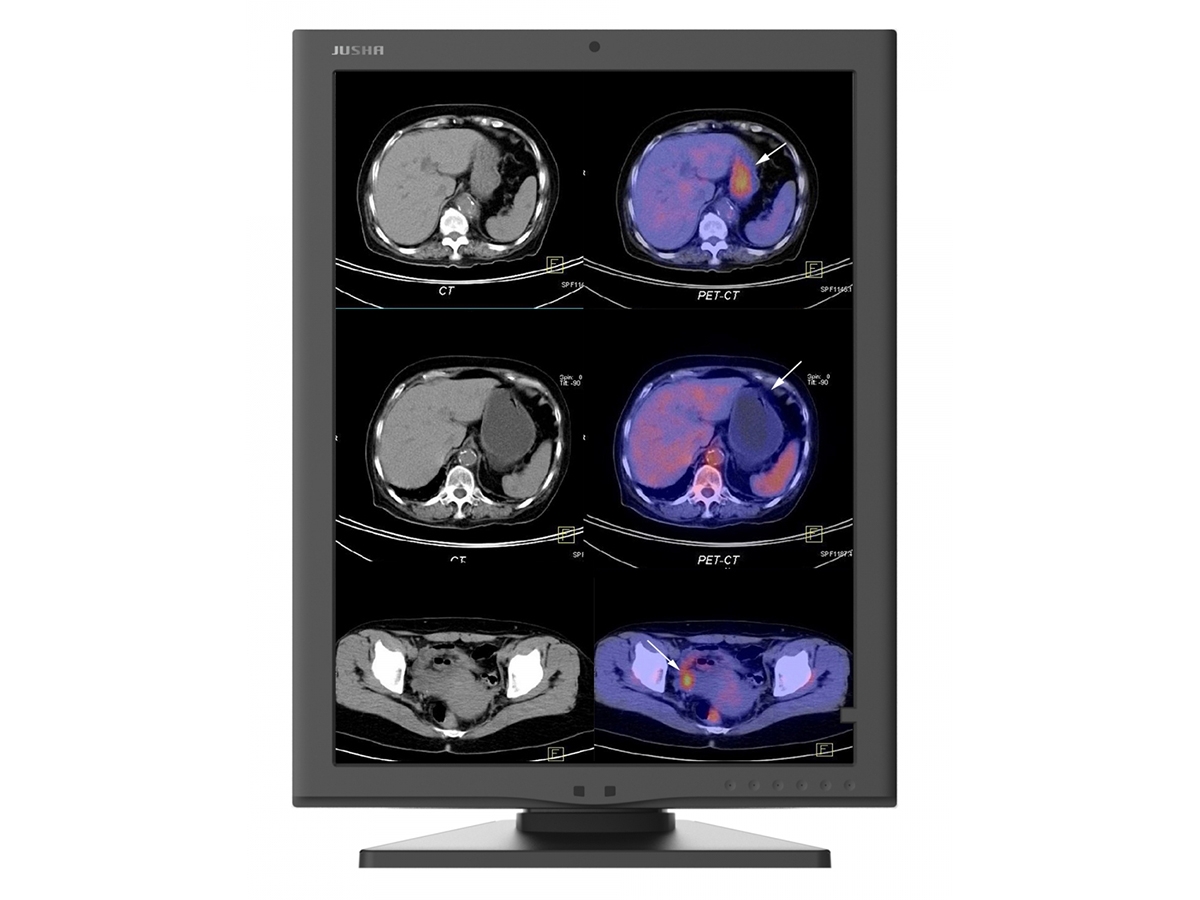

Цветной медицинский монитор C270G с расширением 2 Мп выводит черно-белые и цветные изображения и может применяться с различным медицинским оборудованием для получения медицинских изображений и в различных отделениях медицинских учреждений. С его помощью можно выводить подвижные цветные изображения и черно-белые изображения, соответствующие стандарту DICOM, такие как двухмерные цветные медицинские изображения, слитые, функциональные и объемные изображения.

C270G обеспечивает постоянную яркость в течение всего срока службы и поддерживает многоразовую калибровку в соответствии со стандартом DICOM. Благодаря встроенной 16-битной таблице преобразования соответствует требованиям к высокой точности медицинских изображений.

Высокая яркость Яркость профессионального медицинского дисплея JUSHA может достигать 1000 кд / м 2 . Благодаря сочетанию высокой яркости и отличного контраста создается значительное ощущение глубины, идеально подходящее для определения местоположения очагов;

Высокая градация серого Монитор имеет 16-битную таблицу LUT, которая может отображать оттенки серого 65536 градаций и обеспечивает более плавный переход изображения. Профессиональный дисплей JUSHA гарантирует идеальное отображение 16-битного изображения в оттенках серого, снятого высококлассным оборудованием. Также полезно диагностировать раннее поражение при низком контрасте с нормальными тканями;